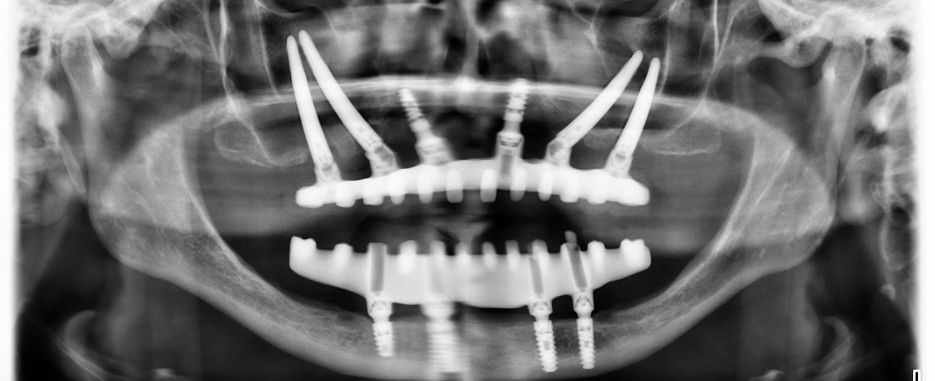

Por otro lado, están los implantes cigomáticos, que se recurre a ellos ante la falta ósea. Estos se centran en el hueso del pómulo, específicamente en el arco cigomático, en donde se anclan, suponiendo para el paciente un periodo más corto de recuperación, así como la prevención de posibles complicaciones. Precisamente, esta técnica es más recomendable en personas mayores.